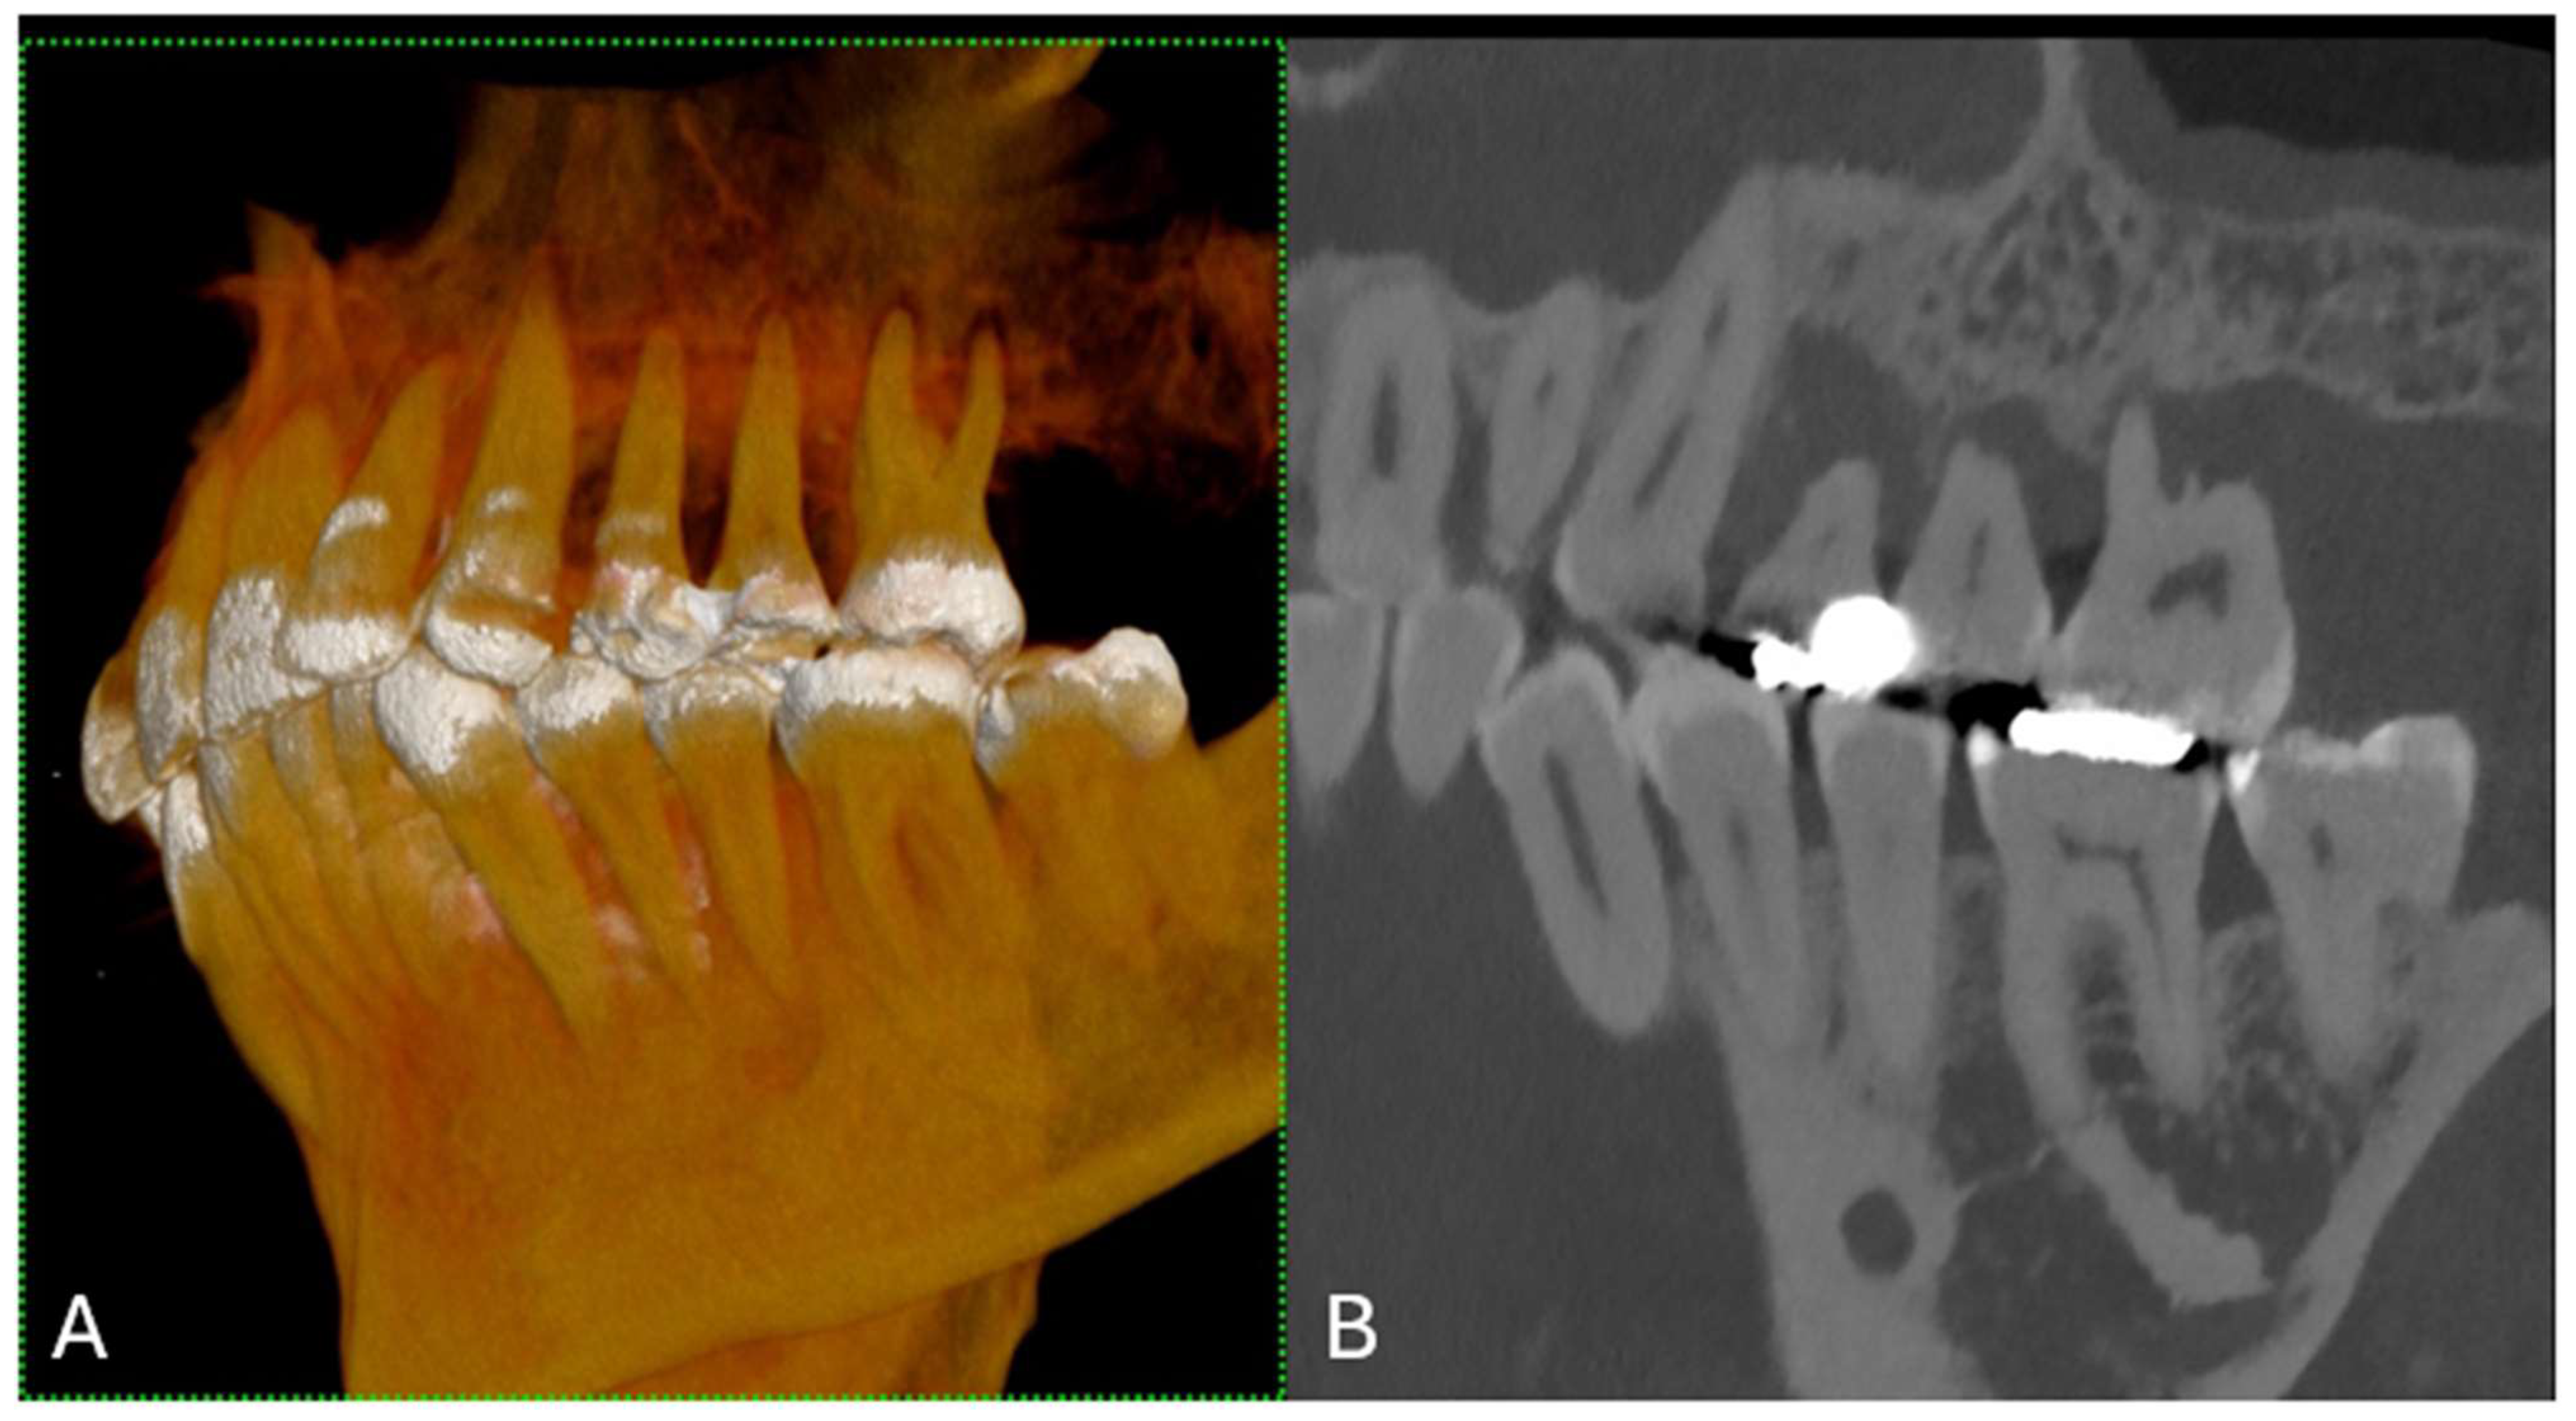

Metal implants in traditional CT scans often create artifacts that can lead to misdiagnosis owing to obscured images resulting from photon starvation, scattering, and beam hardening [7]. PCCT introduces new artifact reduction methods that enhance diagnostic imaging in patients with dental and orthopedic implants [8]. These techniques include Iterative Metal Artifact Reduction (iMAR), which methodically reduces artifacts; high kilo-electron volt (keV) virtual monoenergetic imaging (VMI) for clearer images; and sinogram inpainting to improve image quality around implants [9]. These advances allow for the more precise visualization of dental structures and decrease the prevalence of misleading artifacts (Figure 3).

Figure 3. (A) A longitudinal MPR (A) and panoramic view of the upper and lower jaws, displaying a metallic dental prosthesis. Unlike conventional CT, there are no metal artifacts. (B) A curved MPR image of a portion of the jaws, highlighting a detailed view of several teeth and their respective roots. (C) The 3D cinematic rendering, providing a realistic perspective of the teeth’s condition and alignment, including the dental implant. The scan was performed on a commercial whole-body Dual Source Photon Counting CT scanner (NAEOTOM Alpha, Siemens Healthineers); 0.2 mm slice thickness, 0.1 mm reconstruction increment, FOV 140 mm, spiral acquisition with tube current modulation; resolution matrix of 1024 × 1024 pixels on the source axial reconstructions VIM at 190 KeV. The actual displayed resolution is 0.1 mm (100 microns). Abbreviations: 3D, Three-Dimensional; VMI = Virtual Monoenergetic Imaging; FOV = Field of View.